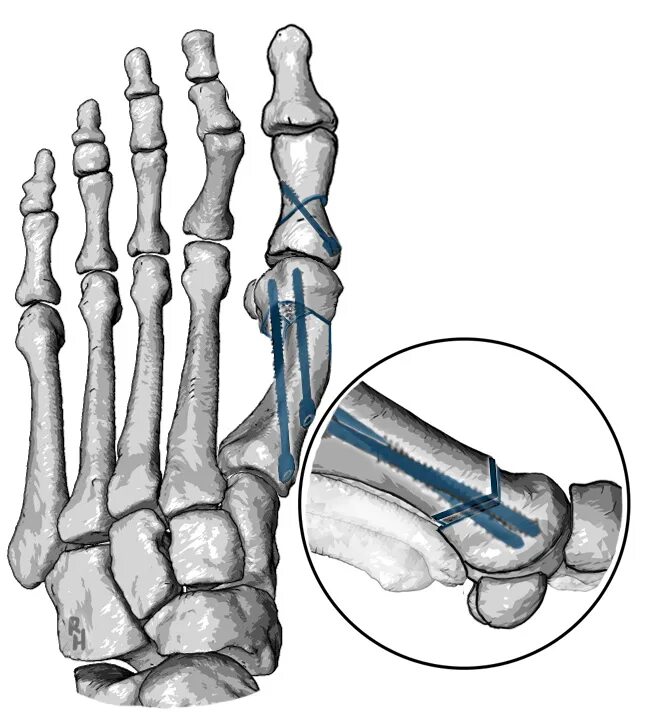

Пяточная остеотомия